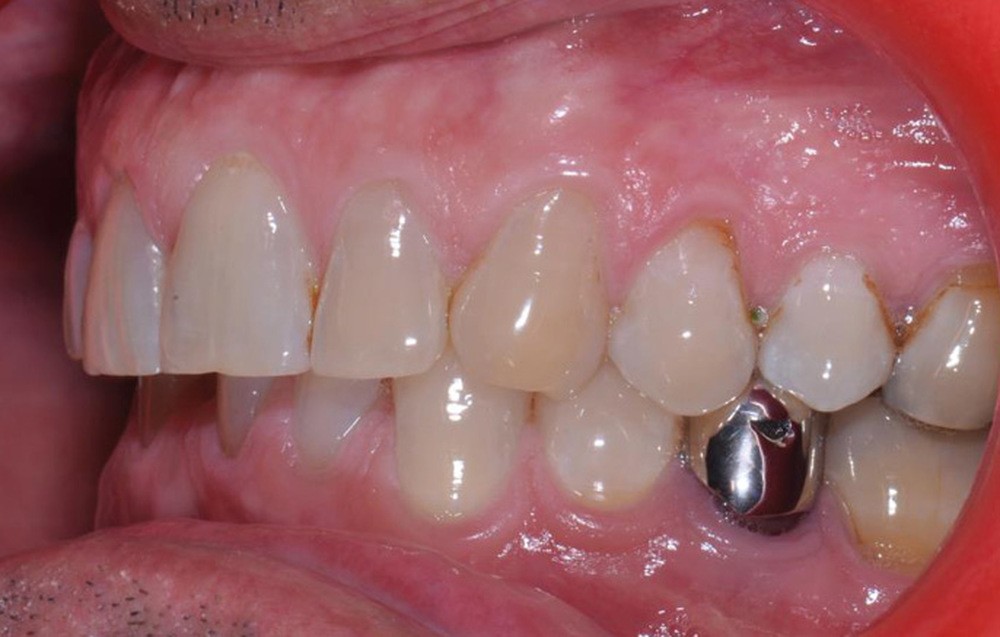

Le plan de traitement établi conjointement avec son chirurgien-dentiste traitant consiste à réaliser un alignement dentaire mandibulaire et à réaliser des extractions de 16 et 15 pour un remplacement par prothèse implanto-portée.

Un accompagnement par des meulages occlusaux est réalisé.

Les techniques orthodontiques de déplacement par gouttières orthodontiques thermoformées sont très efficaces pour gérer des situations simples. Ce patient en montre l’intérêt, en particulier lorsque la forme d’arcade dentaire doit être maintenue. Les systèmes « in-office » peuvent tout à fait permettre la gestion de ces situations.